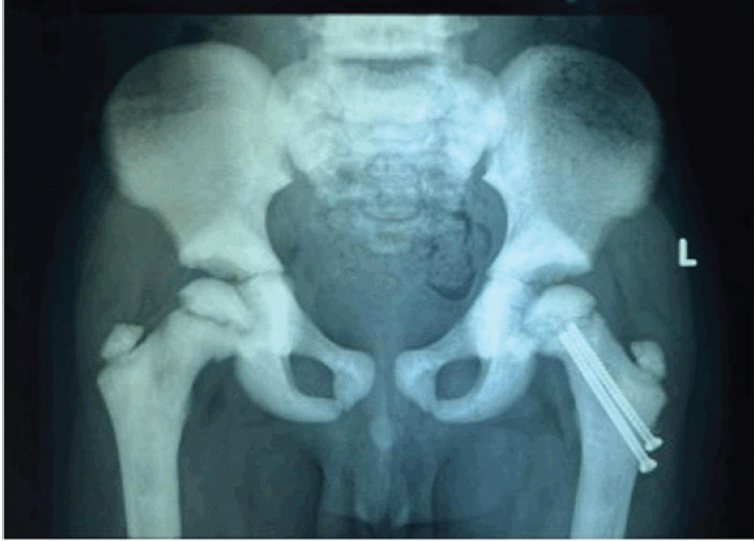

Postoperatively, a hip spica cast was applied for 7 weeks. After removal of the hip spica cast, gradual physiotherapy and progressive weight-bearing were initiated under clinical supervision. Follow-up radiographs after cast removal showed satisfactory fracture healing (Fig. 3).

Figure 3: Radiograph at 7-Weeks follow-up after Hip Spica Cast removal showing progressing fracture union without evidence of avascular necrosis.

At 3 months, the fracture had united without evidence of avascular necrosis or non-union (Fig. 4), and the child had a painless full range of hip movements. Full weight-bearing ambulation was initiated.

Figure 4: Radiograph at 3-month follow-up showing progressing fracture union without evidence of avascular necrosis.